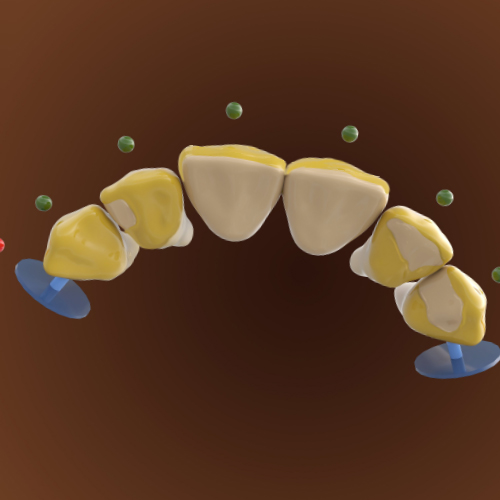

Dental Rehabilitation of the Atrophic Maxilla

Ankur Johri, DDS, MD, FACS

Friday, July 29, 2022

This Compendium eBook features a continuing education (CE) article presents important diagnostic and treatment planning principles of the All-on-4 treatment concept for the rehabilitation of the atrophic maxillary arch, and includes a case report illustrating free-hand implant placement using this treatment approach.